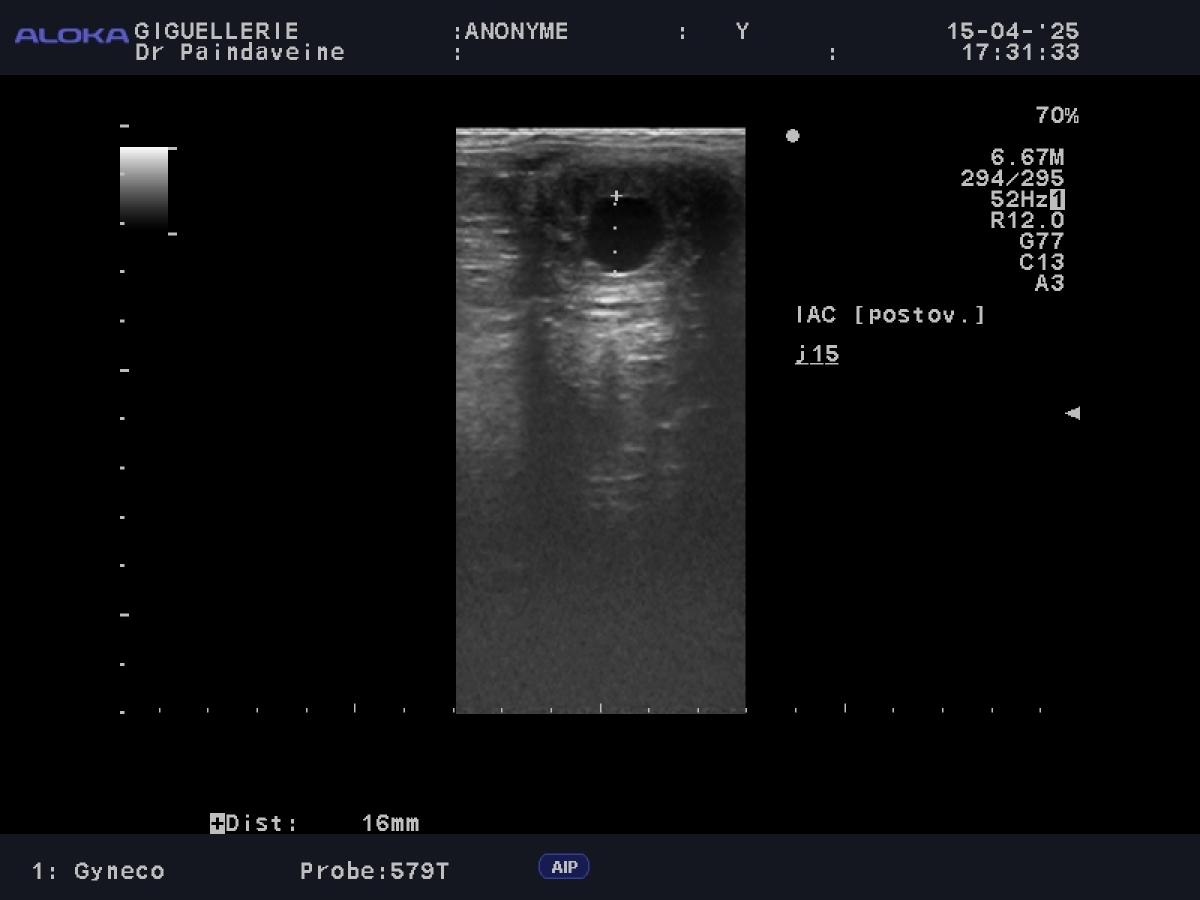

• Eierstöcke: Überwachung der Follikeldynamik zur Vorhersage des Eisprungs und zur Erkennung funktioneller Anomalien (persistierende Gelbkörper, Zysten).

• Gebärmutter: Kontrolle des Tonus und der Gebärmutterumgebung. Besonderes Augenmerk legen wir auf das Fehlen übermäßiger postovulatorischer Ödeme oder Endometritis, die Hauptfaktoren für frühe Resorptionen sind.

Während die Besamung mit Frisch- oder Kühlsperma eine gewisse Flexibilität bietet, erfordert der Einsatz von Gefriersperma (TG) chirurgische Präzision. Da die Überlebenszeit kryokonservierter Spermien verkürzt ist, wird die Überwachung intensiviert, um eine Besamung so nah wie möglich am Eisprung zu gewährleisten.